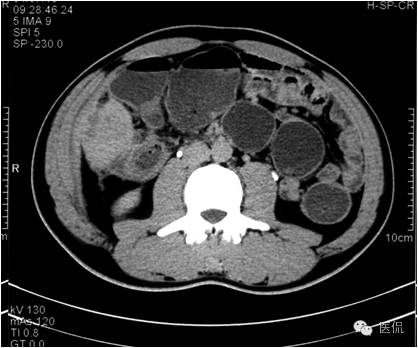

平扫示肝下缘局部隆突,密度减低,内部密度不均,隐约见分隔影,其下缘与升结肠界线消失,肠壁增厚、模糊。

动脉期病灶显示小片状低密度影内,见不规则环状、核心样点状和间隔轻度强化,形态多种。